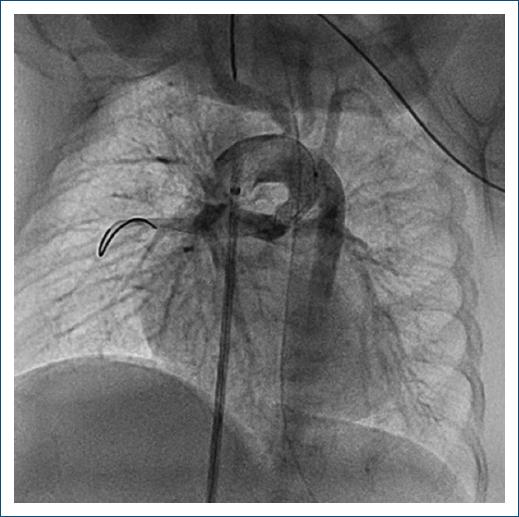

Los procedimientos fueron llevados a cabo en el servicio de hemodinamia del Hospital Garrahan, formado por cuatro hemodinamistas con años de experiencia en el tratamiento de cardiopatías congénitas de pacientes recién nacidos. La distribución de los casos fue similar entre estos. Todos los pacientes fueron planteados para el procedimiento luego de realizar el diagnóstico inicial con ecocardiograma. En algunos casos fue necesario realizar angio-TC con contraste para definir adecuadamente la morfología del conducto, y en unos pocos casos el cateterismo diagnóstico inicial se utilizó para plantear la posibilidad de implantar un stent ductal. En la actualidad se encuentra protocolizada la realización de angio-TC en aquellos pacientes en quienes se plantee la colocación de un stent en el conducto arterioso para definir con mayor certeza la morfología ductal. En los casos que correspondía se suspendió el goteo de prostaglandinas 12 horas antes para favorecer la constricción pulmonar. Para el procedimiento, todos los pacientes requirieron anestesia general con asistencia respiratoria mecánica. En la mayoría de los casos el acceso vascular utilizado fue tanto arterial como venoso, y los introductores oscilaron entre 3 y 5 Fr. En cuatro pacientes el acceso arterial fue carotídeo por el origen del conducto arterioso desde el tronco braquiocefálico. Se utilizaron stents coronarios no farmacológicos con diámetros entre 3.5 y 4.5 mm y de longitud variable. En siete casos fue necesario el implante de dos stents para mantener la permeabilidad del conducto arterioso (Figs. 1 y 2). Al finalizar el procedimiento se efectuó angiografía de control para certificar el buen funcionamiento del stent y su permeabilidad, y luego, con una saturación acorde al modelo hemodinámico, se finalizó el procedimiento y los pacientes pasaron a la unidad de cuidados intensivos (Fig. 3). Posterior al procedimiento se encuentra protocolizado mantener anticoagulación con heparina por 48 horas y luego iniciar antiagregación con ácido acetilsalicílico.

Figura 3 Angiografía tras la angioplastia con un stent en un conducto arterioso originado en el arco transverso en un paciente con atresia pulmonar con comunicación interventricular.